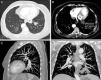

Consolidation, ground glass opacities and a focus of fat density were seen in the left lower lobe (LLL) on chest CT (Fig. 1).

Bronchoscopy and tumor markers were negative for malignancy. Bronchoalveolar lavage (BAL) fluid analysis revealed lipid-loaded macrophages.

The patient reported daily use of liquid Vaseline to facilitate changing and placing her tracheotomy cannulas. After discontinuing this practice, partial resolution of the opacity described was seen on radiological follow-up X-ray at 3 months.